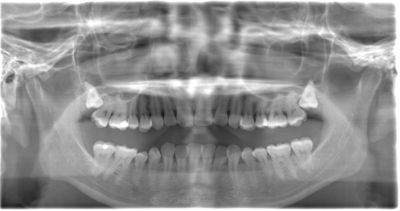

CASE 1

| 年齢・性別 | 30代・女性 |

| 主訴 | 左右に分けて親知らずを抜きたい、できれば痛くなく抜きたい |

| 親知らずのはえ方 | 完全に出ていてまっすぐはえている |

| 抜歯期間 | 15分 |

| 抜歯費用 | 約2,000円(保険内) |

| 抜歯内容 |

何度か虫歯になり痛みはないが早めに抜きたい。 完全に頭が出ているため歯ぐきを切ったり骨を削らずに抜歯しました。 根の形も単純なため抜歯自体は5分もかからず上下ともに終わりました。 術後痛みや腫れも出ていません。 抜歯後は感染をしやすいため必ず抗生物質を飲み切ってください。 |